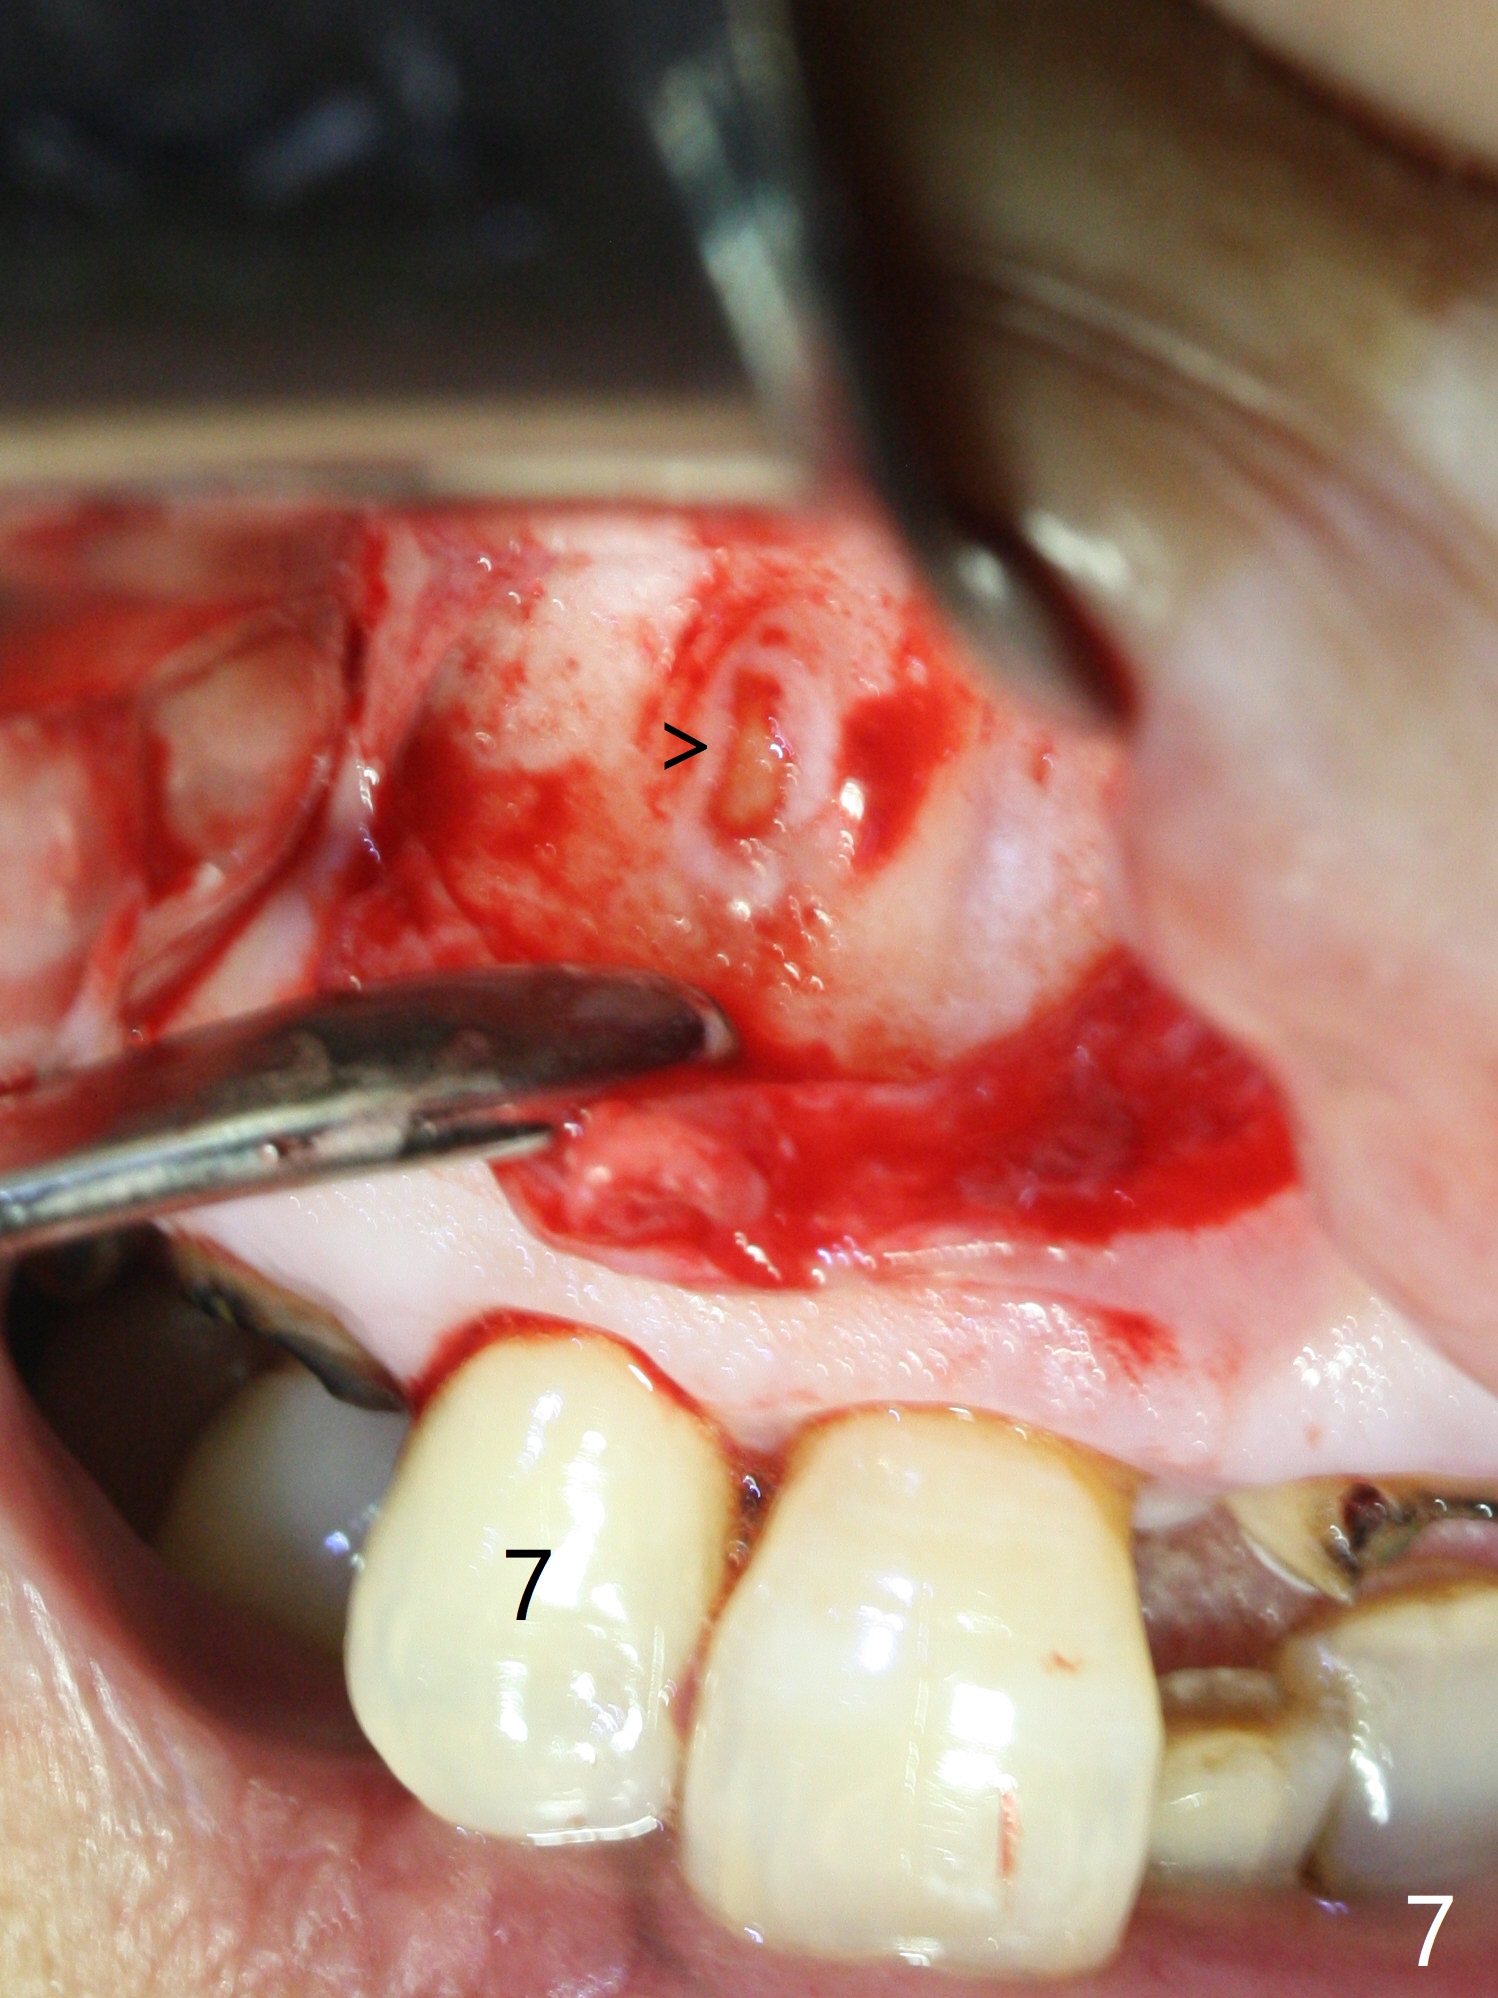

A 86-year-old woman with diabetes (under control with Insulin) and poor dentition (Fig.1) presented to clinic with an abscess apical to the tooth #8 (nonvital, Fig.2). CBCT (Fig.3) or PA (Fig.4) does not show radiolucency at #7 or 8. The incised abscess with purulent drained is superficial to the apparently intact periosteum (Fig.5 *). The patient is reluctant to have #7 and 8 extracted, since they are the only remaining functional dentition. The infection recurs 1.5 months later (Fig.6 * (^: previous incision)). With the periosteum elevated, fenetration over the apex of the tooth #7 (vital in pulpal test) is only seemingly significant finding (Fig.7). The abscess (Fig.8 A) is shown superficial to the periosteum (*). The infection is expected to relapse. What should be done otherwise? Full mouth extraction has been discussed.